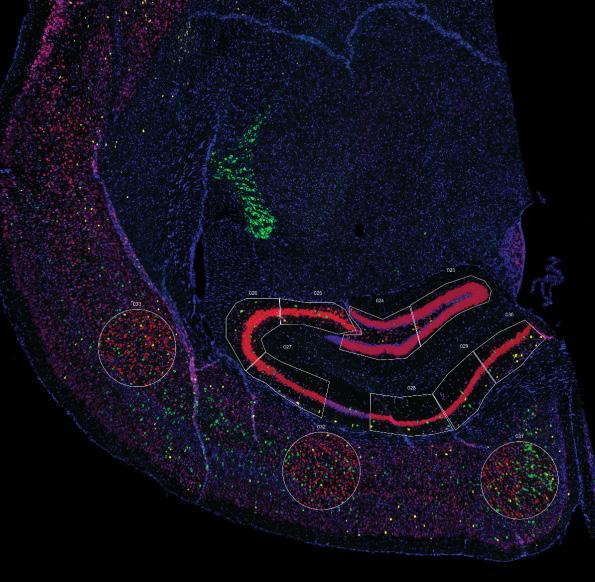

Dr. Wajd Al-Holou

Dr. Wajd Al-Holou, director of the Brain Tumor Microenvironment lab (https://al-holou.lab.medicine. umich.edu), was recently awarded the very prestigious NIH K08 Award, which will help to support some of the very critical work in his laboratory studying malignant brain cancers. His lab studies the intersection of spatial biology, genetics, cutting-edge therapeutics, and patient care and is focused on identifying new insights into these tumors and developing new treatment options. On the clinical side, Dr. Al-Holou who also serves as the co-director and co-founder of the Michigan Medicine Multidisciplinary Brain Tumor Clinic (M3BTC), has expanded access to this clinic to twice per week by teaming up with amazing clinicians within Neurosurgery, Radiation Oncology, and NeuroOncology.

Safiulla Syed, PhD, a postdoctoral fellow in Dr. Al-Holou’s Brain Tumor Microenvironment Lab received the 2025 ChadTough (Defeat DIPG Foundation) Fellowship Grant for a project titled “Targeting mechanisms of treatment resistance in diffuse midline glioma,” which will be overseen by mentors Dr. Al-Holou and Dr. Rehemtulla (Radiology).